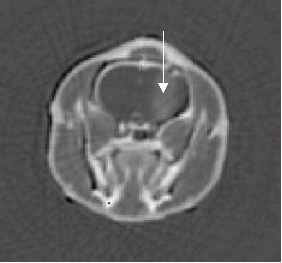

After each irradiation, we made an image with an iodinated contrast agent to verify if the rats effectively had a tumor (see figure).